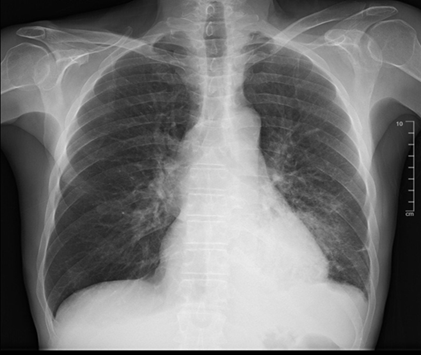

Figure 4. First cxr

post-discharge; left subclavian chest port with the tip in the svc. The heart

is stable in size. There is pulmonary venous congestion without overt edema.

Redemonstrated is a large mass like opacity in the left lower lobe with a small

left pleural effusion. No pneumothorax. The right lung is clear.

Upon discharge, he was educated on the importance of taking

his medications for copd, specifically his albuterol and ipratropium

nebulizers. Four days after discharge from our facility, he received a

single-lumen power port vascular catheter through the left subclavian vein for

chemotherapy. An outpatient cxr showed mild pulmonary venous congestion without

overt edema with a stable, large, mass-like opacity in the left lower lobe. Our

patient was given close follow up with hematology-oncology, pulmonology, and

primary care to optimize his management for stage iva nsclc.